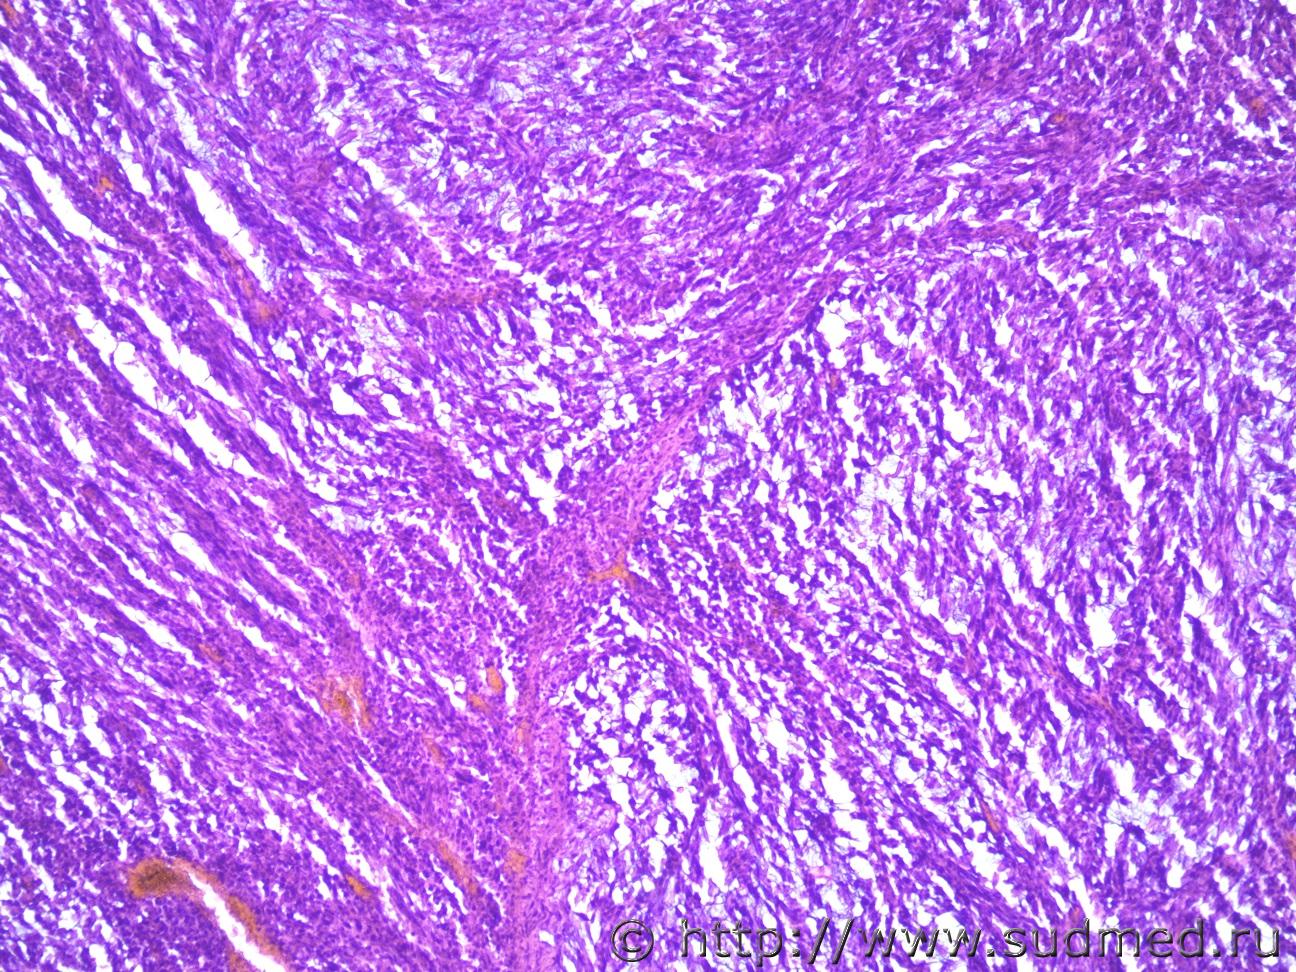

Ув. коллеги столкнулась с проблемой. легкие - опухоль, метастазы? вопрос от танатолога, в легких очаги слизистой консистенции. У меня вопрос это что-то из слизеобразующих опухолей или очаги пневмонии на подобии клебсиеллезной?

Посмотрите на просвет соседних альвеол и на межальвеолярную перегородку между "образованием" и соседними альвеолами. Мне видятся они полностью интактными, что не очень укладывается в воспалительную природу.

Больше сответствует на плевролегочную бластому...

Муж 88 лет

Да легкие на границе интактные, есть отдельно еще кусочки легких из каких мест взятые не знаю, тоже спокойные, в одном мелкоочаговая гнойно-фибринозная пневмония. В двух сосудах не в кусочке с образованием такие же массы (метастазы, тромбы?) Судебная медицина - Прикрепленное изображение

В Международной гист.классификации опухолей лёгких есть так называемый муцинозный рак (8480/3).

Возможно,это он и есть."Картинки" похожи.

Раковые эмболы.

Эмболизация в сосудах имеет место. Клетки с баллоновидно-пузыревидной оптической цитоплазмой и нежноволокнистой безядерной стромой. Но не наблюдается сецернирующих призматических эпителии. Было бы влажный материал не лишнее было бы покрасить на Судан-3. Надеюсь о чем можно думать, ясно.